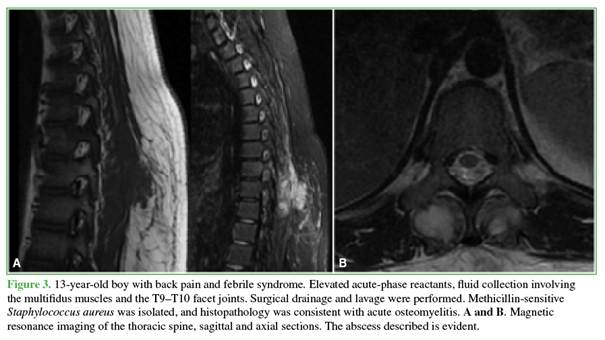

Abscesses associated with spondylitis resolved with antibiotic treatment, whereas the remaining abscesses required surgical drainage, including those in two children whose diagnosis in the emergency department was made exclusively by ultrasound. Staphylococcus aureus was isolated in seven patients (p = 0.001), including four cases of MRSA and three of MSSA (Figures 3-6).

Magnetic resonance imaging showed hypointense signal on T1-weighted sequences and hyperintense signal on T2-weighted and STIR sequences, with gadolinium enhancement. In patients with bone involvement and negative blood cultures, image-guided needle biopsies were performed: three percutaneous transpedicular biopsies, one transfacet biopsy, and one transoral biopsy. In two cases, no pathogen was identified; in two cases, S. aureus was isolated (1 MRSA and 2 MSSA). All specimens submitted for histopathological analysis were classified as acute osteomyelitis (Figures 8 and 9). According to protocol, all specimens were evaluated for tuberculosis (Figure 10).